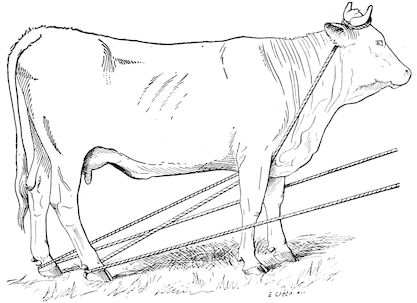

Accidental and local diseases of the apparatus of locomotion are matters of less urgency in the case of cattle than in that of the horse. On the other hand, general affections, such as rheumatism and osseous cachexia, demand a larger share of attention, and are of the utmost importance.

As the accurate diagnosis of any disease demands careful and systematic examination, the practitioner usually observes a certain order in his investigations, as indicated below:—

(1.) Inspection, from the side, from the front and from behind, reveals the existence of deformities of bones, limbs, muscles and joints, articular displacements, and irregularities of conformation or of gait.

By inspection of an animal as it walks various forms of lameness, and their particular characteristics, are rendered visible.

(2.) Palpation and pressure will detect changes in local sensibility, the softness or hardness of tissues, the existence of superficial or deep fluctuation, œdematous swelling, and abnormal growths like ring-bones and exostoses, as well as the exact character of articular enlargements.

(3.) Percussion is of little value in examining the apparatus of locomotion. Nevertheless, percussion of the claws, and of certain bones of the limbs, or of flat bones, may afford valuable information in cases of laminitis, ostitis, and periostitis. Percussion along the longitudinal axes of the limb bones is also useful in diagnosing intra-articular fractures, subacute arthritis, osteomyelitis, etc.

(4.) The gait. Lame animals should be made to move, in order to assist both in discovering the cause, and in estimating the gravity of the condition. Sometimes it is advisable to turn the animal loose, but most frequently it is moved in hand, either in straight lines or in circles.

2Information so obtained should always be supplemented by local manipulation and by passive movement, such as flexion, extension, abduction, adduction and rotation of the joints.

A knowledge of the characteristics of normal movement in any given joint, renders it comparatively easy to detect abnormality, such as increased sensibility, articular crepitation or friction, and to diagnose fractures with or without displacement, ruptures of tendons or ligaments, etc.